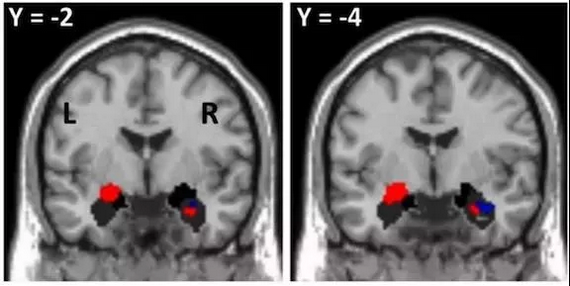

上文也提到,英國研究人員發現人類討厭高頻尖銳的聲音,是因為大腦中的杏仁體。杏仁體是大腦邊緣系統的皮質下中樞,主要功能是調節內臟活動和產生情緒等。研究人員認為,杏仁體是人類在進化的過程中保留的與動物比較相似的結構,是恐懼記憶建立的神經中樞。

當大腦出現各種焦慮、緊張、暴躁、憤怒等反應時,杏仁體就會充當起指揮官的角色,指揮身體做出反應。